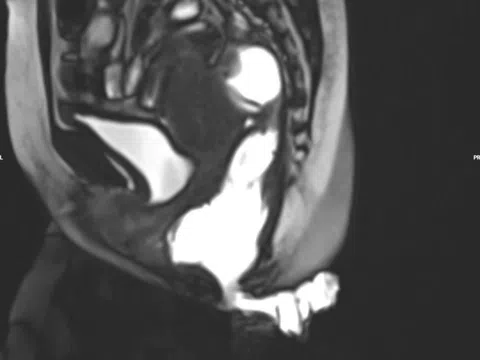

Đau tức hạ sườn, ăn kém, sút cân… là dấu hiệu bệnh gì?

00:01 08/01/2026

U máu gan là dị dạng mạch máu bẩm sinh và là khối u lành tính hay gặp nhất ở gan. Nhiều người nhập...